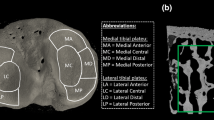

Several studies investigate other measures of bone microarchitecture and topology from HR-pQCT images, including connectivity, SMI, and anisotropy; however, there is mixed evidence of their reliability at in vivo resolutions [23, 93, 97, 136]. Recently, more sophisticated approaches to cortical bone segmentation have been proposed [18] that allow direct three-dimensional assessment of cortical thickness and quantification of cortical ultrastructure (Fig. 5), including intracortical porosity and canal diameter [24, 111]